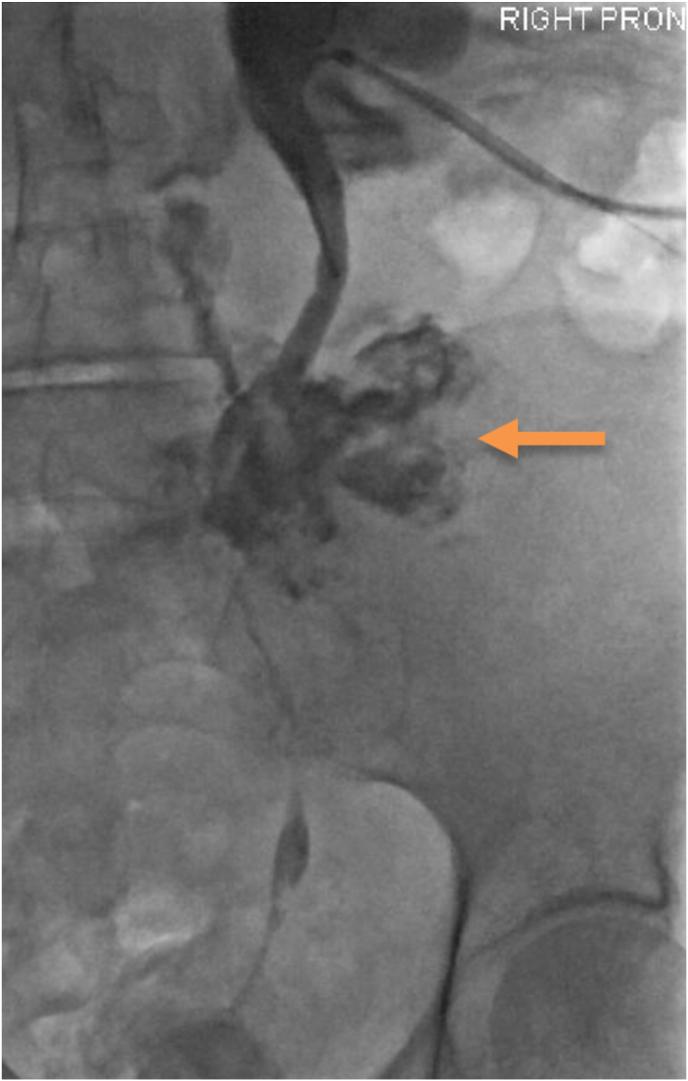

A rare complication of urinary catheter insertion: Proximal ureteric rupture and sepsis.

Unintended Foley's catheter placement into the ureter: A case report.